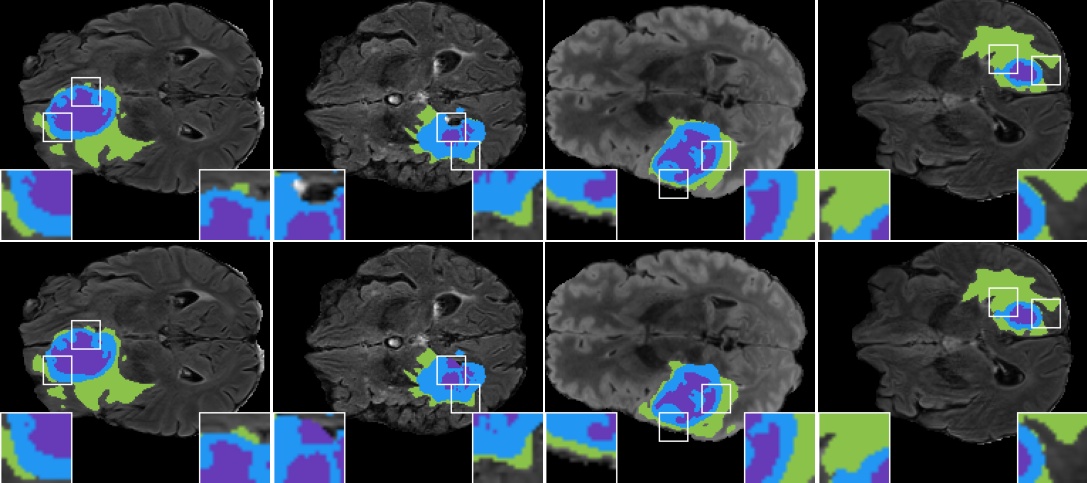

We show some qualitative results of our segmentation predictions in Figure4.